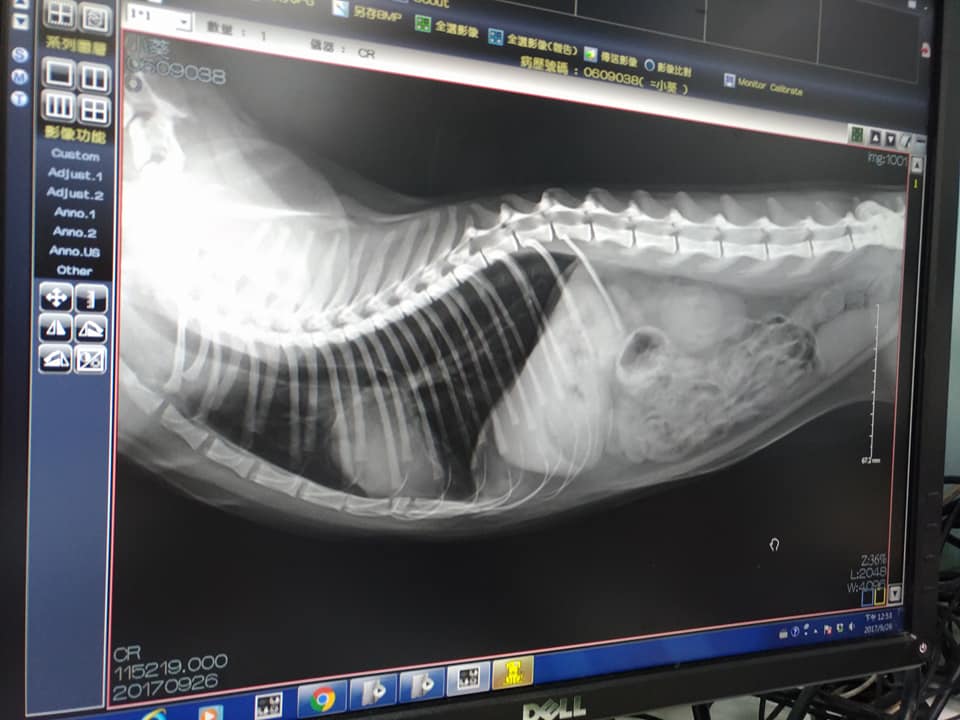

9/26沐恩初診 小葵 3.6KG(跟年初比是瘦了)

口炎嚴重,前小牙都已鬆動,犬齒牙齦痿縮,無疝氣,X光也無大礙。在醫院有流口水的現象。呼吸聲比較大,可能是鼻腔跟喉頭比較窄的關係,鼻腔的X光,必須要鎮靜才能做。